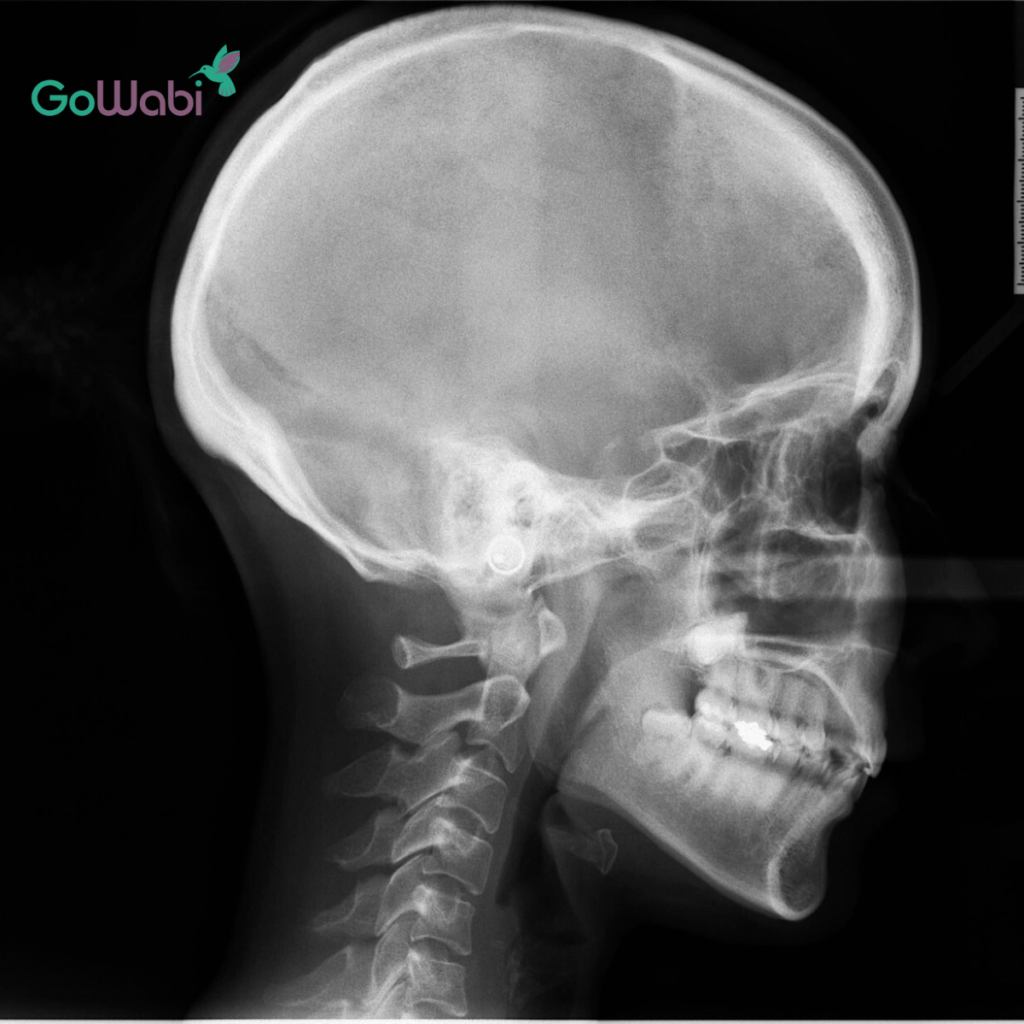

1. ปรึกษาและตรวจประเมินฟัน

ฝ้ายเริ่มจากการจองคิวเข้าปรึกษากับ DCA Dental Clinic สาขาสุขุมวิท 49 คุณหมอจะทำการตรวจเช็กฟันของเราอย่างละเอียด ว่าปัญหาฟันของเราสามารถแก้ไขด้วย Dr Clear Aligners ได้หรือไม่ ซึ่งปัญหาที่ฝ้ายเป็นกังวลก็คือ ฟันซ้อน ฟันเก ค่ะ

หลังจากนั้นก็ทำการสแกนฟันแบบ 3D เพื่อดูโครงสร้างฟันของเราผ่านคอมพิวเตอร์ และทำแผนการรักษาให้เห็นล่วงหน้าว่าฟันของเราจะค่อย ๆ ขยับไปตำแหน่งไหนบ้าง